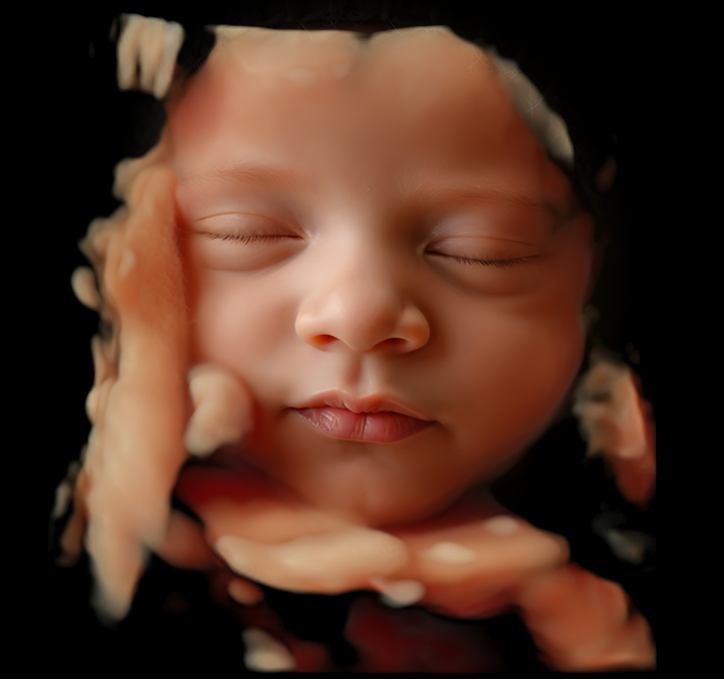

In 3&4D de baby zien blijft natuurlijk heel erg bijzonder. Samen met de familie kijken op wie de kleine lijkt en wat er allemaal in je buik gebeurd is zo speciaal. Het maakt het allemaal nog echter, omdat het soms zo moeilijk te bevatten is dat er zo’n klein wonder in je groeit. De mooiste periode om de baby in 3&4D te bekijken is tussen de 27 en 30 weken zwangerschap.

Ook na de 30 weken maken we vaak nog hele mooie beelden, het is natuurlijk ook gewoon een beetje geluk hebben. Dus mocht je twijfelen kom dan altijd gewoon proberen, mocht het niet lukken en denken we dat het ook niet meer gaat lukken, dan betaal je alleen de even spieken echo!